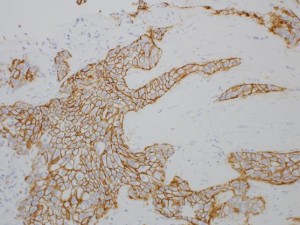

生検標本組織診断;浸潤性乳癌

分子標的治療;HER-2(茶色に染色された細胞)